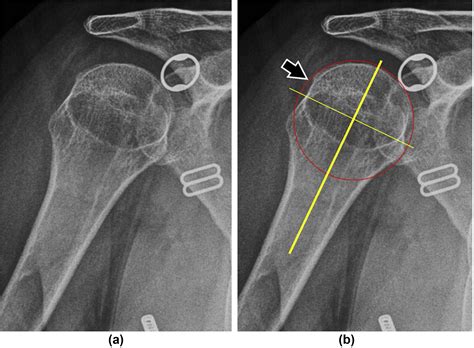

• Imaging studies: X-rays, MRI, or CT scans may be used to visualize the shoulder joint and confirm the presence of a Hill Sachs Lesion. These imaging studies can also help determine the size and location of the lesion, which is important for treatment planning.

In some cases, additional tests, such as arthroscopy, may be necessary to fully evaluate the extent of the injury and plan appropriate treatment.